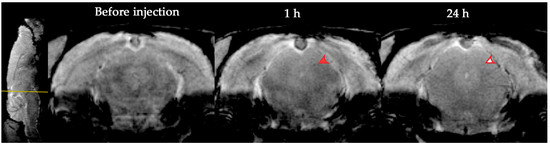

3.1. Dynamic MRI Distribution of MSCs in Ischemic Rat Brain after Intravenous Transplantation